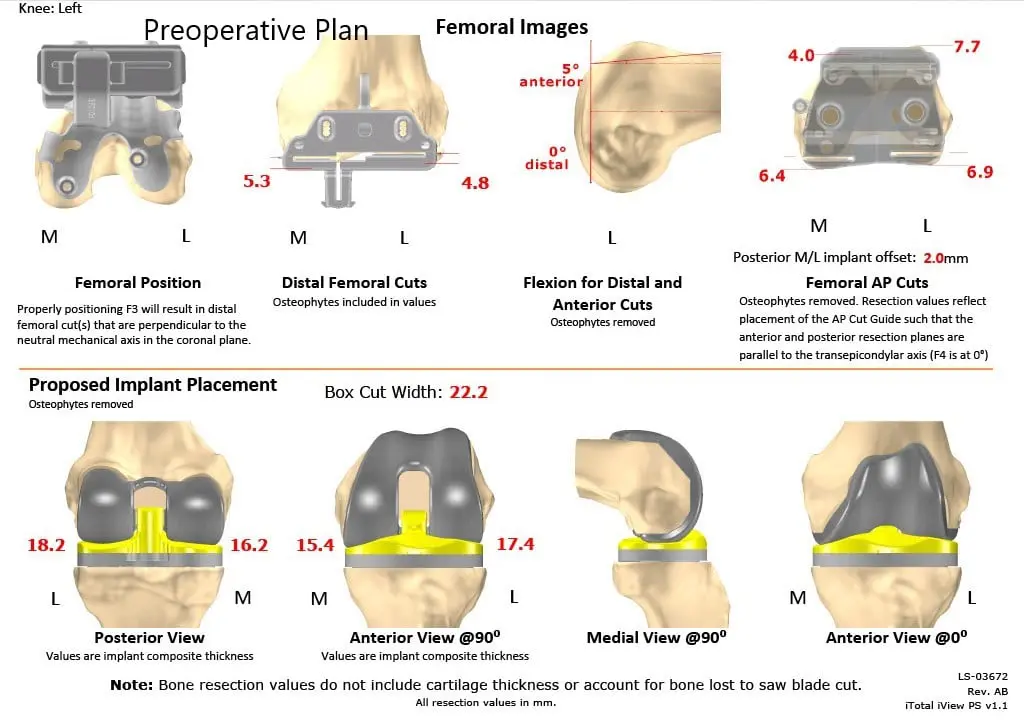

Imaging studies demonstrated medial joint space narrowing with degenerative changes. A CT scan of the patient’s left knee with hip and ankle was obtained a few weeks before the surgery demonstrating tricompartmental osteoarthritis. The data from the CT scan were used to create a 3D model of the patient’s anatomy. The data was then used to create custom implants and custom instruments.

Custom implants and instruments offer surgeons to have perfect alignment and recreation of the joint line before the disease process with bone preservation. A custom patient-specific plan was provided detailing the sizing and cuts of the procedure for accurate alignment. Disposable 3 D printed jigs were to be used designed uniquely for the patient to create bone resection. The details were outlined in a preoperative plan.

Complete Orthopedics patient-specific surgical plan for a left custom knee replacement in a 67-year-old female (scan 2)